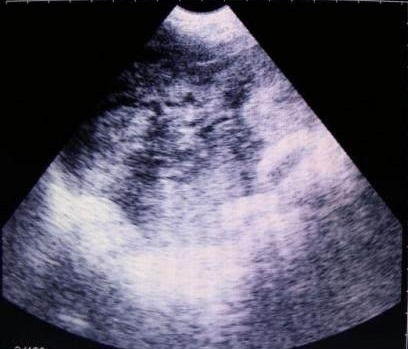

母豬B超檢測空懷圖片

獸用B超機檢測母豬空懷圖像